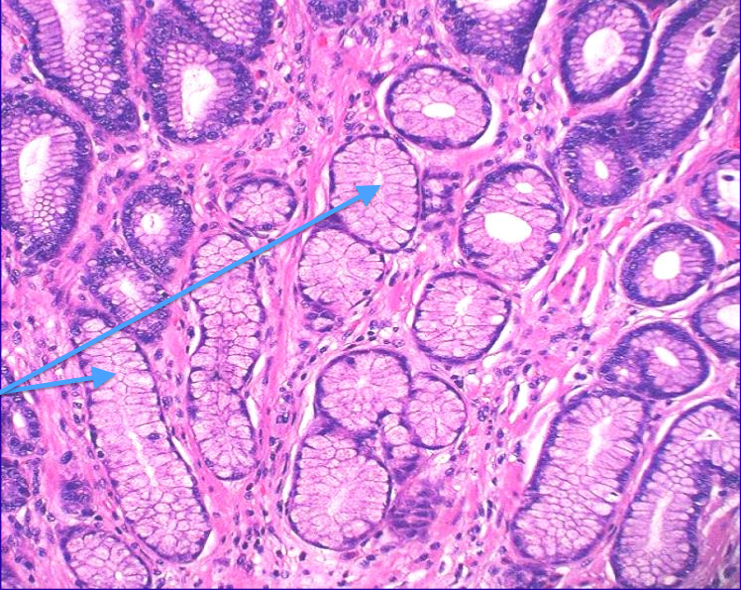

<p>What type of glands are shown here? Describe them</p>

<p>oxyntic; combination of both basophilic and eosinophilic cells</p>

<p>What type of glands are shown here? Describe</p>

<p>mucin glands, pale and eosinophilic</p>